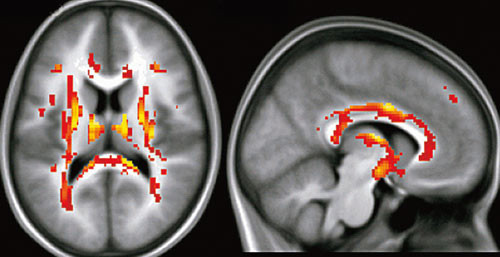

Ved hjelp av såkalt diffusjonstensor-MR visualiserte man organiseringen av hjernefibersubstansen hos barn med svært lav fødselsvekt (1). I hjernens hvite nervefibersubstans er vanndiffusjonen mye større på langs enn på tvers av nervefibrene. Dette kommer av at cellemembraner og myelinskjeden lager en barriere. Metoden kan derfor benyttes til å kartlegge arkitekturen eller organiseringen av mikrostrukturen i hvit substans.

– Vi fant at barn med fødselsvekt < 1 500 g hadde en rekke områder i hvit substans hvor det var mer uorden, dvs. mindre ensretting av nervefibrene. Disse områdene, som bl.a. inkluderte capsula interna og capsula externa, corpus callosum og de lange assosiasjonsbanene, så normale ut på vanlig konvensjonell MR, men representerte mikroskader i hvit substans som var oppstått i perinatalperioden, sier barnelege og professorstipendiat Jon Skranes ved Norges teknisk-naturvitenskapelige universitet.